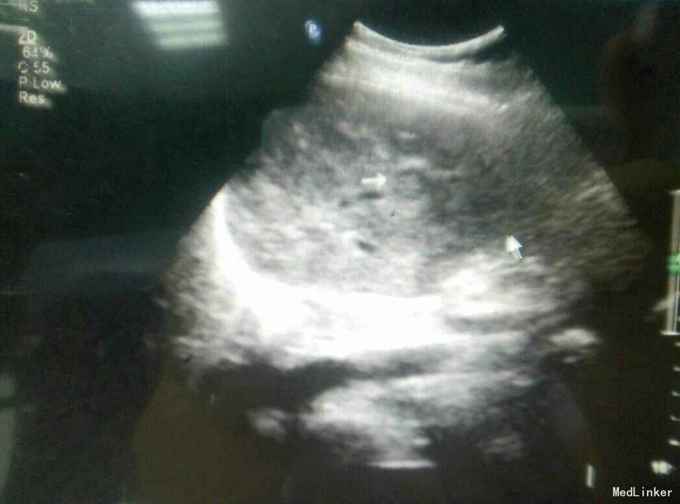

患者,女,43岁,左乳癌术后2年余,发现肝脏占位3天

查体:未及明显异常 辅助检查:腹部彩超发现肝脏多发占位,考虑转移,腹部增强CT:肝脏多发结节,考虑乳腺癌肝转移

随访与讨论:患者入院时肝功能就偏高,也算是一个肝功能受损征相,而且彩超检查发现门静脉有癌栓形成,说明比较晚期,预后不良,所以采取姑息性辅助化疗,希望可以减轻患者病痛。当然同时也要排除其他地方转移,以采取相关治疗措施。